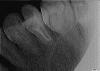

костерико Опубликовано 18 марта, 2010 Автор Поделиться Опубликовано 18 марта, 2010 (изменено) Сходила взяла снимки в эл.виде.Будьте добры посмотрите каналы,как сделаны.И все-таки я не понимаю,не развод ли это был.Где там два канала?И зубы,которые справа и слева от анкерного-их состояние.Если конечно качество подходит.Добавлю 4 снимка,какой лучше не знаю. Изменено 18 марта, 2010 пользователем костерико Ссылка на комментарий

zybnaya feya Опубликовано 18 марта, 2010 Поделиться Опубликовано 18 марта, 2010 это что то новое........это уже вторая переделка и что опять не переделали хорошо?а все так думают?я сейчас в обморок упаду.вообще зуб уже не болит,хотя,при постукивании по нему,он неприятно чувствителен(((А ТРЕТИЙ РАЗ МОИ КАНАЛЫ ОСИЛЯТ? Костерико,вы хоть бы пронумеровали сним. Где ДО ,а где ПОСЛЕ?? Если тот что самый последний,так он мутный и не информативен. Все остальные я так поняла сделаны ДО последнего (второго)вмешательства? Ссылка на комментарий

костерико Опубликовано 18 марта, 2010 Автор Поделиться Опубликовано 18 марта, 2010 (изменено) Костерико,вы хоть бы пронумеровали сним. Где ДО ,а где ПОСЛЕ?? Если тот что самый последний,так он мутный и не информативен. Все остальные я так поняла сделаны ДО последнего (второго)вмешательства?нет,все СНИМКИ СДЕЛАНЫ ПОСЛЕ ПЛОМБИРОВКИ каналов.НА НИХ ГОТОВЫЙ РЕЗУЛЬТАТ.доктор все сделан, потом рентген,сказал все супер. Изменено 18 марта, 2010 пользователем костерико Ссылка на комментарий

zybnaya feya Опубликовано 18 марта, 2010 Поделиться Опубликовано 18 марта, 2010 нет,все СНИМКИ СДЕЛАНЫ ПОСЛЕ ПЛОМБИРОВКИ каналов.НА НИХ ГОТОВЫЙ РЕЗУЛЬТАТ.доктор все сделан, потом рентген,сказал все супер.Если ЭТО окончательная пломбировка,то +10000 к мнению Fury Канал не пролечен до апекса(а их 2) и весь просвет в порах,что свидетельствует о его вустотк в просвете. Очень жаль это говорить-но перелечивать его надо снова Ссылка на комментарий